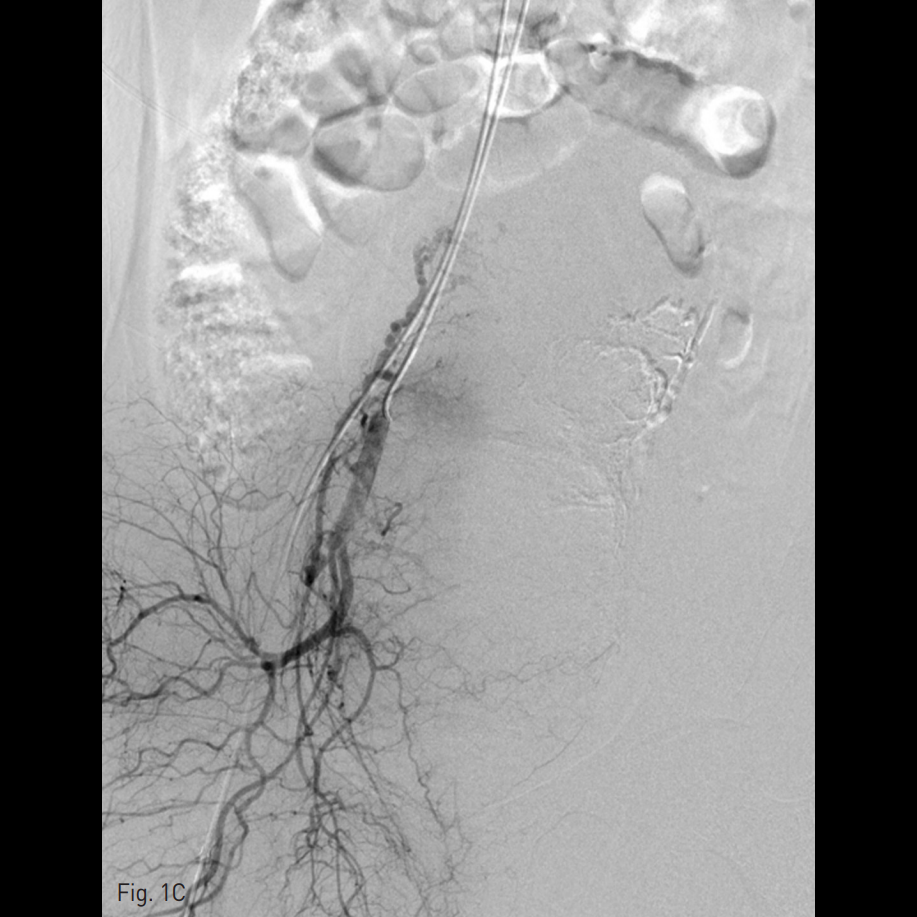

우측 총대퇴동맥을 천자하여 5 Fr sheath를 삽입하고, 5 Fr RUC catheter (Roberts Uterine Catheter, COOK medical, Bloomington, IN, USA)를 이용하여 좌측 내측 장골동맥을 선택하여 조영술을 시행한 뒤 좌측 자궁동맥을 선택하여 조영술 시행하였으며 (Fig. 1A), 출혈의심소견이 있어 gelfoam을 이용하여 색전술을 시행하였다 (Fig. 1B). 이후에 시행한 우측 내측 장골동맥을 선택하여 조영술을 시행한 뒤 (Fig. 1C), 우측 자궁동맥을 초선택하여 조영술을 시행하였을 때, 우측 자궁동맥이 비후되어 있어, gelfoam을 이용하여 색전술을 시행하였다. 색전술 직후 산부인과 진찰에서 지속적인 출혈소견이 보였다. 이에 5 Fr pigtail catheter를 이용하여, 대동맥 조영술을 시행하였다. 하장간막동맥 (Inferior mesenteric artery)으로 부터 출혈 소견이 관찰되었다 (Fig. 2A). 이에 대해서 2.2 Fr 마이크로카테터 (Progreat, Terumo, Japan)를 이용하여 하장간막동맥을 초선택하여 코일(Nester microcoil, COOK Medical, Bloomington, IN, USA)과 gelfoam (Spongostan, Ferrosan Medical Devices, Denmark)을 이용하여 색전술을 시행하였다 (Fig. 2B). 이후 다시 하장간막동맥 조영술을 시행하여 더 이상의 출혈이 없음을 확인하고 시술을 종료하였다 (Fig. 2C).

Fig. 2

A. Aortogram revealed active extravasation of contrast media from the distal branch of the IMA.

B. Active bleeding was better visualized on angiogram using 2Fr microca theter.

C. Bleeding was controlled after coil embolization.